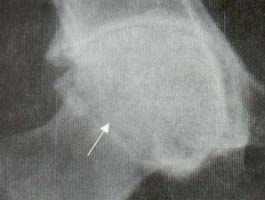

Las articulaciones periféricas más comúnmente comprometidas son: cadera, hombro, rodilla y metatarsofalángicas. Las caderas se comprometen en el 50% de los pacientes y el compromiso se caracteriza por disminución del espacio articular, migración axial de la cabeza femoral, y osteofitos en forma de collar en la unión de la cabeza con el cuello (Figuras 8 y 9).

Figura 8. Cadera. Disminución del espacio articular,

migración axial de la cabeza femoral, esclerosis subcondral acetabular y

osteofitos alrededor de la cabeza femoral (Flecha).